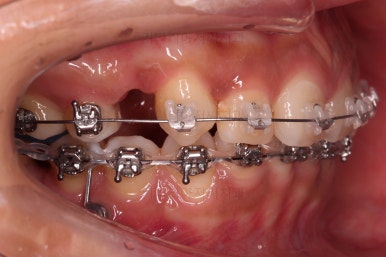

큰 틀에서는 잘 진행 중인 것 같지만 이번 경우처럼 윗니만 발치, 그리고 발치 위치가 다른 경우, 더군다나 아랫니도 어금니가 없고 사랑니를 당겨오는 경우.

미세한 치아 크기 차이로 마지막 마무리가 오래 걸리는 경우가 많습니다.

100% 중앙선이 잘 안맞는 경우가 많고 미세한 틈새가 오랫동안 잘 안닫히기도 합니다.

이번 환자분도 마찬가지로 중앙선이 100% 안맞았고, 틈새를 타이트하게 닫기 위해 시간이 좀 소요되었습니다.